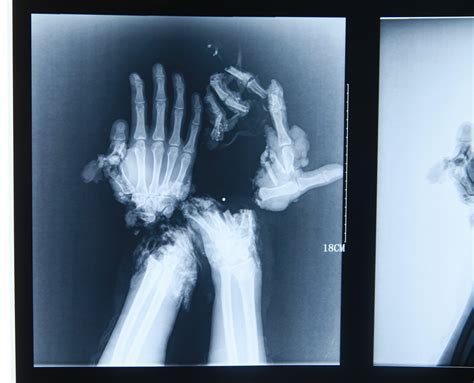

A broken hand x-ray is a type of medical imaging that uses low levels of radiation to produce images of the bones in the hand. These images are crucial for diagnosing fractures, dislocations, and other bone-related injuries. The x-ray machine emits X-rays that pass through the body and are absorbed differently by various tissues. Bones, being denser, absorb more X-rays and appear white on the resulting image, while softer tissues appear darker.

• Displacement: This refers to the misalignment of the bone fragments, which can affect the healing process and may require surgical intervention.

Based on these findings, your healthcare provider will determine the best course of treatment, which may include immobilization, medication, or surgery.

• Scaphoid Fractures: These occur in the scaphoid bone, one of the small bones in the wrist. They are often caused by a fall onto an outstretched hand.

• Distal Radius Fractures: These affect the end of the radius bone in the forearm, near the wrist. They are common in falls and can be quite painful.

• Surgery: In more severe cases, surgery may be required to realign the bone fragments and stabilize them with plates, screws, or pins.